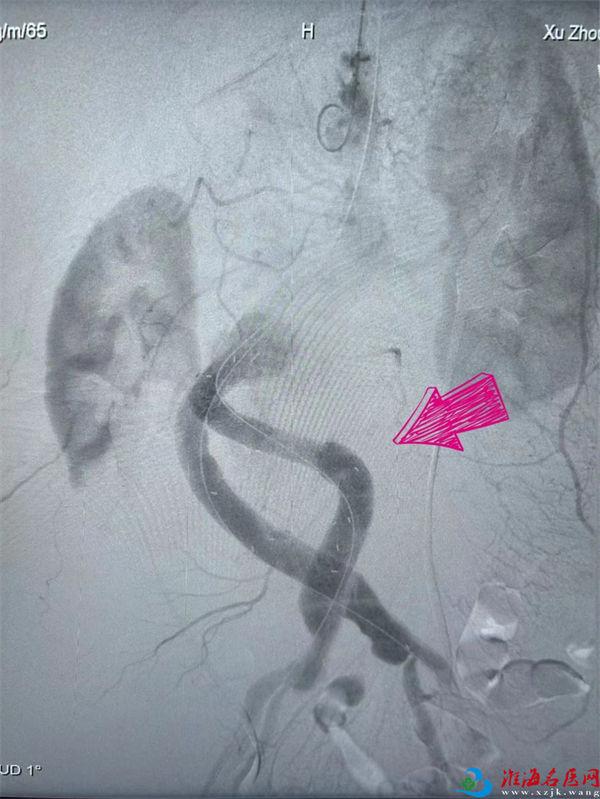

手术紧张有序地进行中,作为心脏大血管外科各类经导管微创介入治疗专家,刘冀东凭借丰富的临床经验和单江桂、王峦默契配合,穿刺、置入导丝、导入主动脉-髂动脉分叉型大血管覆膜支架主体及输送系统并释放、导入髂支分别套叠于主体长短支上并释放抵达左右侧髂总动脉、球囊扩张……每一次操作都精准流畅,每一个手法都熟稔绝妙,每一个步骤都无缝衔接。当看到术后造影显示支架位置良好,覆盖瘤体满意,无明显内漏时,大家悬着的心终于放了下来——“定时拆弹”被成功拆除。这一关,王先生是闯过来了。

术前

术后